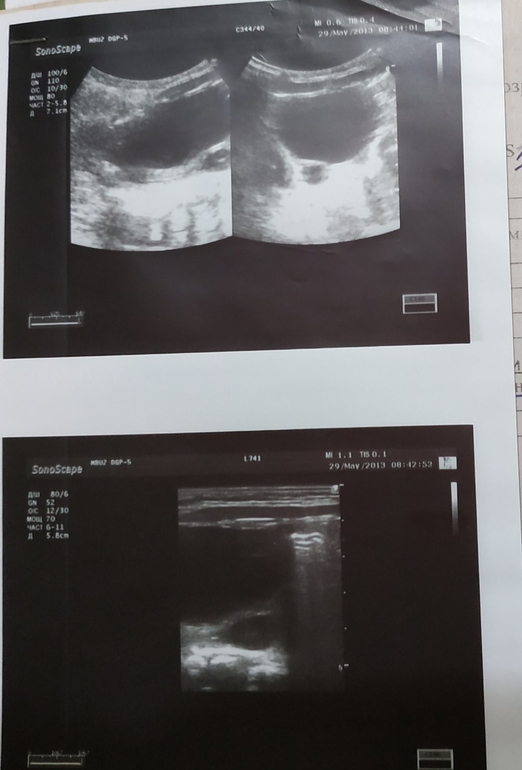

вот последнее узи из платной клиники:

Т.к. на том узи медосмотра в 6 лет мы посикать не смогли (мало накопилось) и показаний после микции не измерили, я переделала узи платно в хорошей клинике, но привела дочь с полным мочевым пузырем, в результате есть показания до и после микции но лоханки шире, левая 13, правая 9, после микции сразу левая 12 правая 6 .